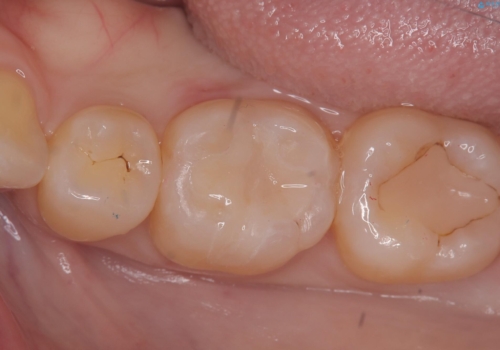

充填されているプラスチックの材料を除去したところ、う蝕が広がっていたため除去しCR裏層の後セラミックインレー修復をしています。セラミックインレーセット時は、ラバーダム防湿を行っています。